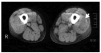

Se inició tratamiento con anfotericina B en dosis de 0,8 mg/kg/día. A los 20 días de tratamiento, con dosis acumulada de 650 mg comenzó con dolor espontáneo en el muslo izquierdo y fiebre. Se constató dolor a la palpación con temperatura local conservada y aumento de tamaño del muslo y región inguinal izquierda. La ecografía del muslo izquierdo puso de manifiesto múltiples imágenes hipoecoicas de bordes anfractuosos, compatibles con colecciones supuradas de diferente tamaño (la mayor de 30 mm de diámetro anteroposterior) a nivel del tejido muscular. La tomografía computarizada (TC) del muslo izquierdo mostró aumento de tamaño en comparación con el contralateral, con imagen hipodensa a nivel del vasto externo extendida al tejido celular subcutáneo vecino y edema perilesional compatible con absceso (fig. 2). Se efectuaron hemocultivos en los que se obtuvo el desarrollo de S. aureus resistente a meticilina. El ecocardiograma no mostró vegetaciones en las válvulas cardíacas. Se inició tratamiento con vancomicina IV a la dosis de 2 g al día. Evolucionó de manera desfavorable con episodios de bacteriemia e insuficiencia respiratoria con acidosis metabólica y deterioro del sensorio. No respondió a dopamina ni a medidas de expansión y falleció.

Figura 2. TC: imagen hipodensa a nivel del vasto externo compatible con absceso.